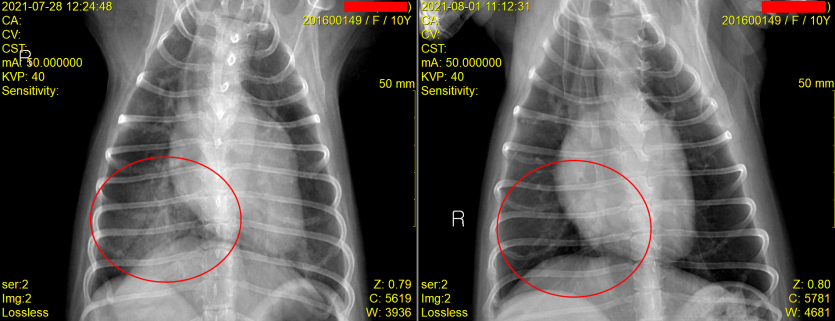

내원 후 흉부 방사선 사진 촬영과 심장 초음파 검사 진행

저희 잠실ON동물의료센터에서는 복슬이의 정확한 증상 파악을 위해 흉부 방사선 사진촬영과 심장 초음파 검사를 진행하였습니다.

다행히 집중적인 입원치료 끝에 11살 말티즈 복슬이는 4일만에 폐수종이 사라지고 건강히 퇴원하게 되었습니다.